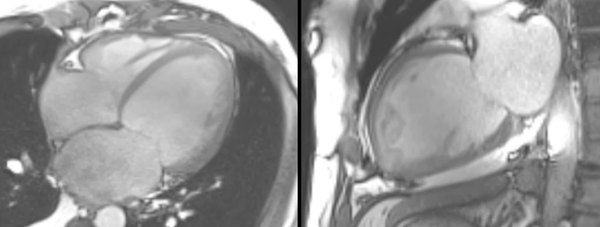

HCM